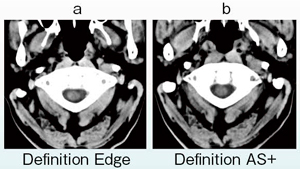

当院では,2013年5月から, Definition EdgeとDefinition AS+の両方で撮影した頭部単純CTについて,深部白質のSD値を測定している。1か月間で撮影した20症例でSD値の平均を比較してみると,Definition Edgeが2.0,Definition AS+が2.2であり,全般的にはDefinition Edgeの方がノイズの少ない画像が得られた。

特に,C1-大後頭孔レベルの脊髄の描出能には大きな差があり,Definition Edgeではきわめて「シャープで切れ味のある(the feel of a cutting edge)」画像が得られた(図7)。基底核領域などの部位でも,良好な画質が得られている。